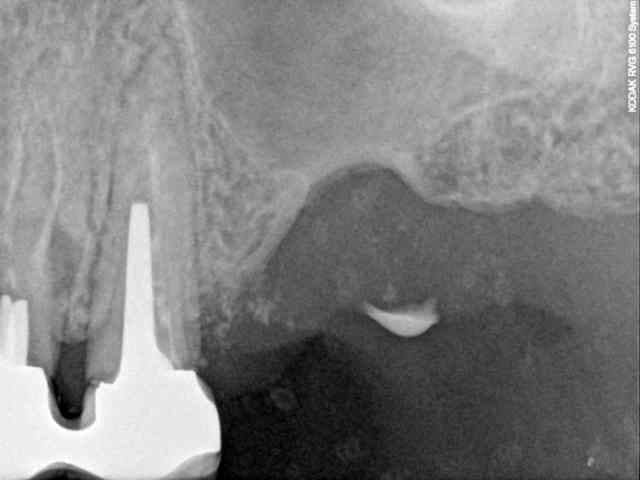

50 ans, fumeuse, belle femme, CBS suite à une malheureuse extraction

fermeture de la cbs par un chir maxillo-faciale à l'aide de la boule de Bichat

6 ans plus tard elle se plaint de gênes à ce niveau.

elle veut des dents.